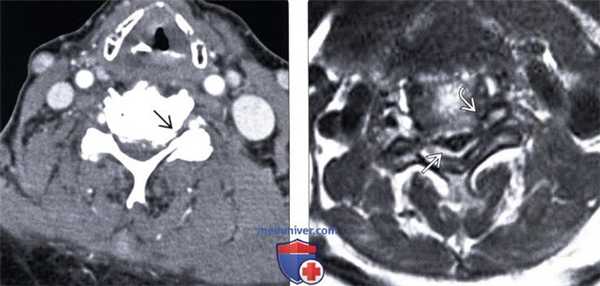

(Слева) На аксиальной МРТ (T2*GRE) определяется умеренный фораминальный стеноз, обусловленный легкими детенеративными изменениями дугоотростчатых суставов и гипертрофией унковертебральных суставов. Гиперинтенсивный сигнал в спинном мозге обусловлен его хроническим сдавлением и миеломаляцией.

(Справа) На аксиальной MPT (Т1ВИ C+) определяется фораминальный стеноз на фоне гипертрофии унковертебральных суставов, дегенеративных изменений дугоотростчатых суставов и миеломаляции с накоплением контраста в спинном мозге.

(Слева) На аксиальном T2*GRE МР-И видны признаки умеренно выраженного фораминального стеноза на фоне относительно легких дегенеративных изменений дугоотростчатых суставов и гипертрофии унковертебральных суставов. Спинной мозг с признаками усиления сигнала вследствие хронического сдавления и миеломаляции.

(Справа) Т1-ВИ с КУ: признаки фораминального стеноза вследствие гипертрофии унковертебральных суставов и дегенеративных изменений дугоотростчатых суставов, в толще спинного мозга виден очаг усиления сигнала, представляющий собой зону миеломаляции.